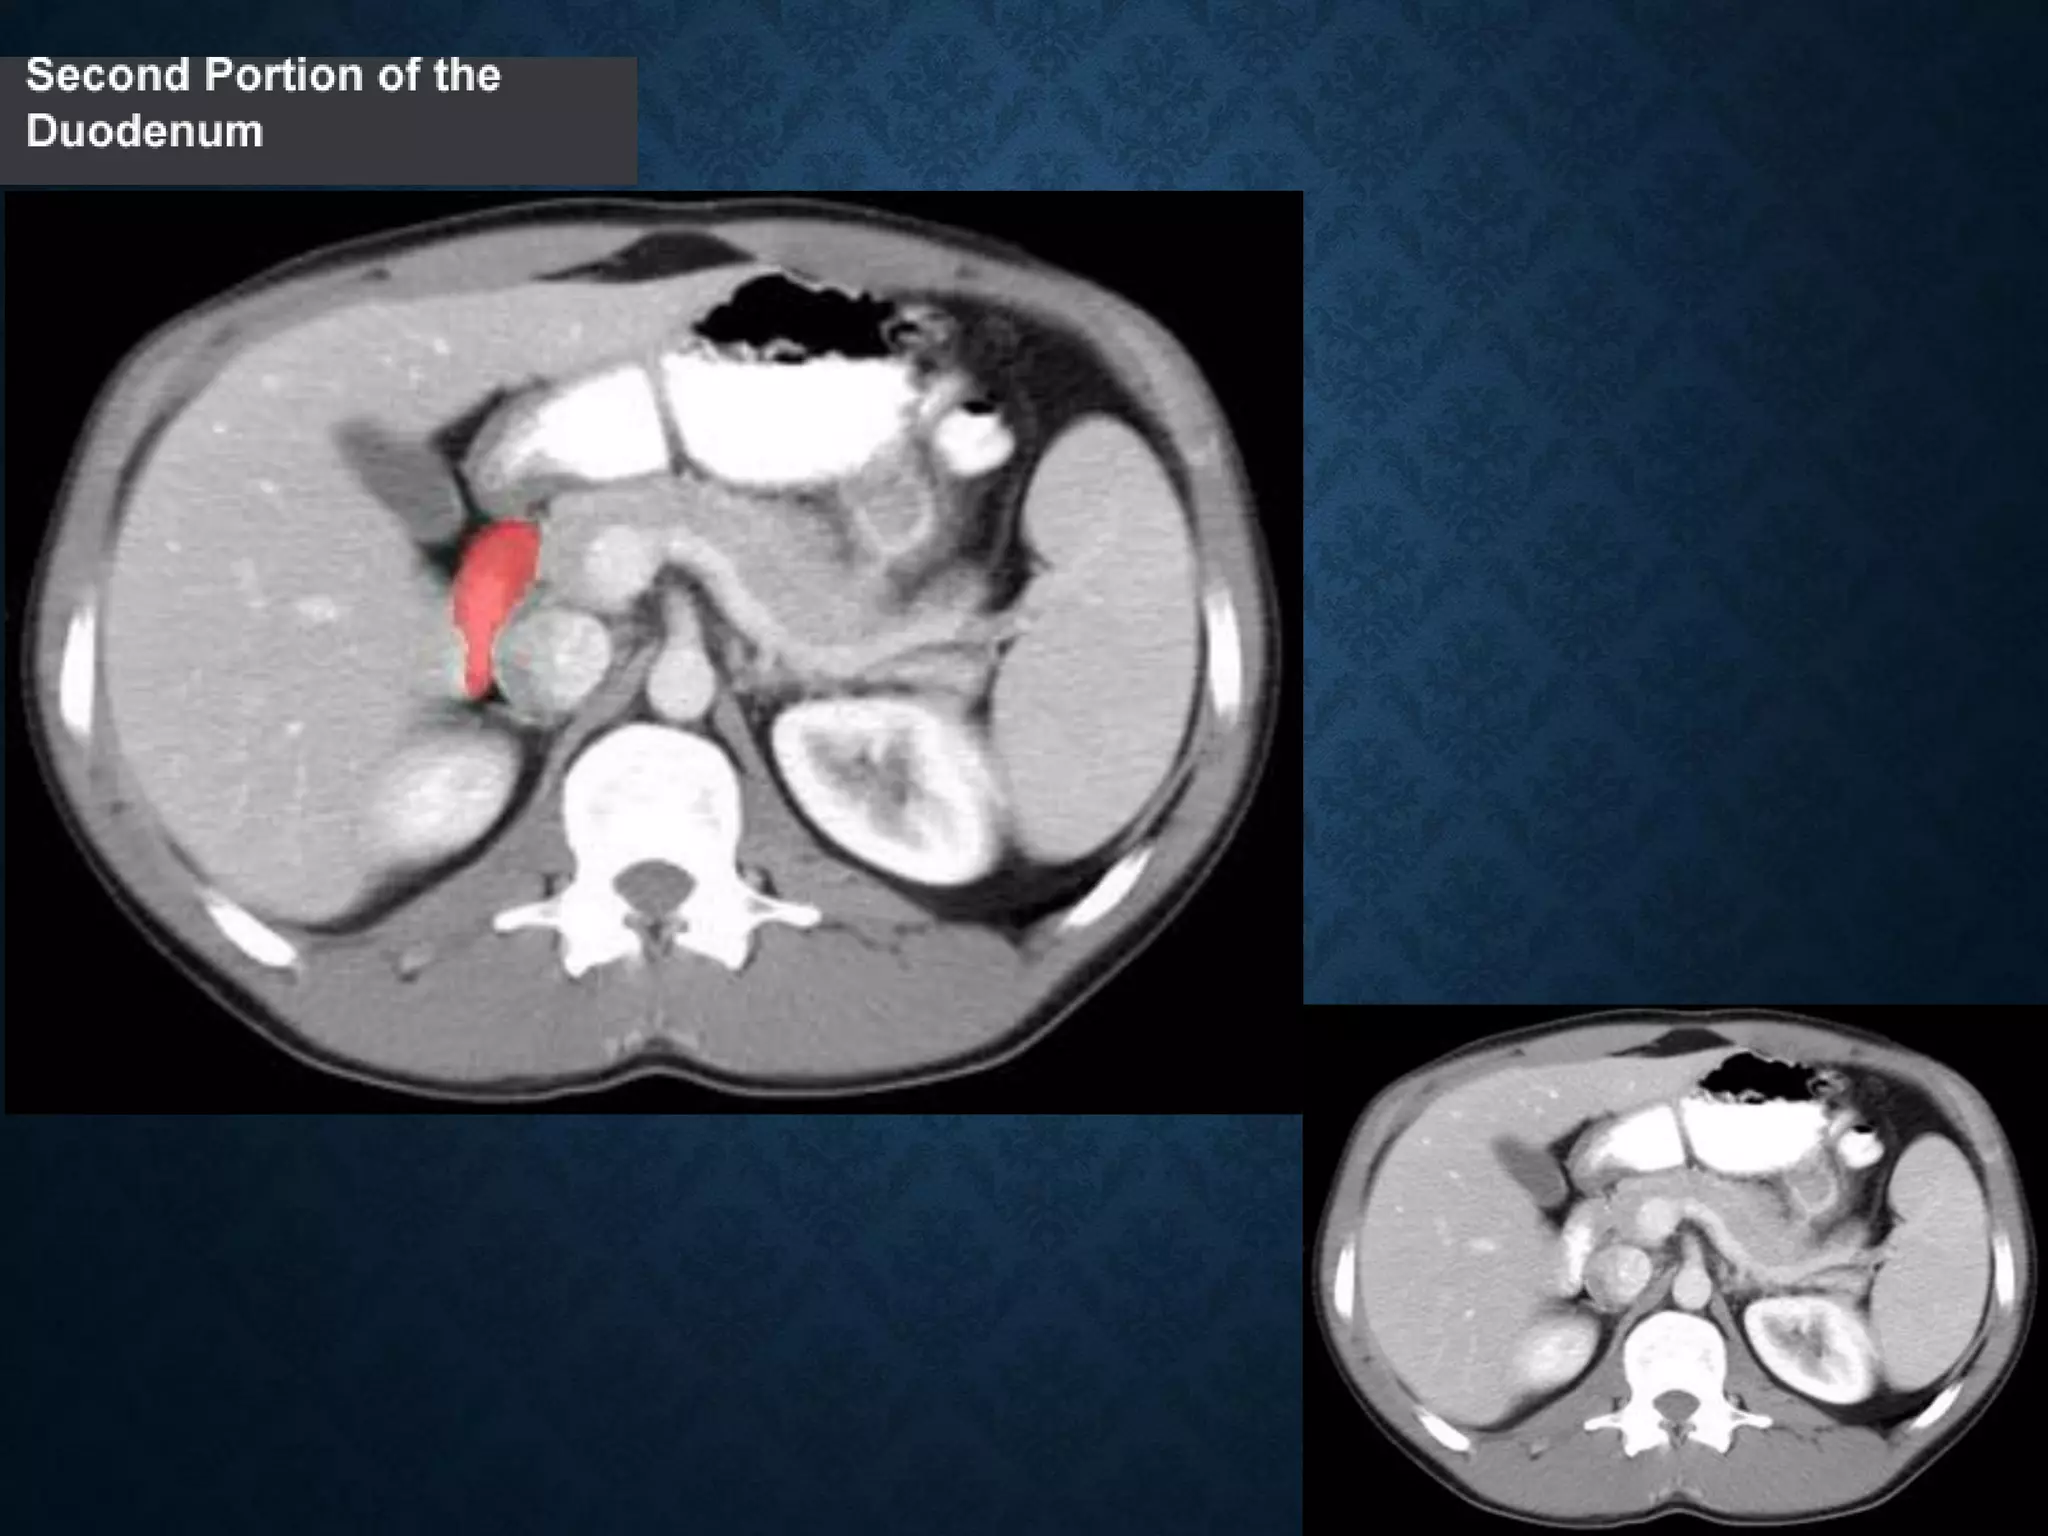

Identify the following structures in the body CT to the right. To view the location of the structure in the image click on

the label at the left and the structure will be indicated in the image. Abdominal CT scans typically begin just above

the diaphragm, so the first slice you see is of the lower chest.

Identify the followingstructures in the body CT to the right. To view the location of the structure in the image click on the label at the left and the structure will be indicated in the image. Abdominal CT scans typically begin just above the diaphragm, so the first slice you see is of the lower chest.